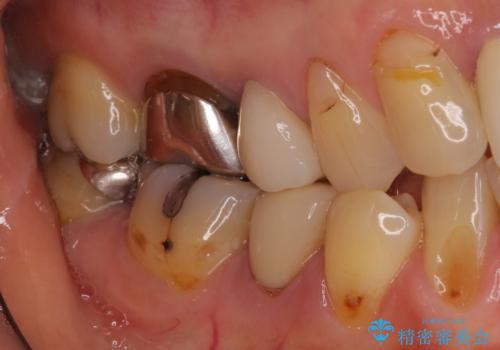

- 目立つ銀歯を気にして来院された患者様です。

奥歯を中心に銀歯が多く装着されており、一部の歯は咬合時に痛みを感じている状態でした。

必要な歯に根管治療を行い、オールセラミッククラウンにて補綴治療を行うこととしました。

一部根管治療では症状が改善しなかったため、歯根端切除術を行いました。